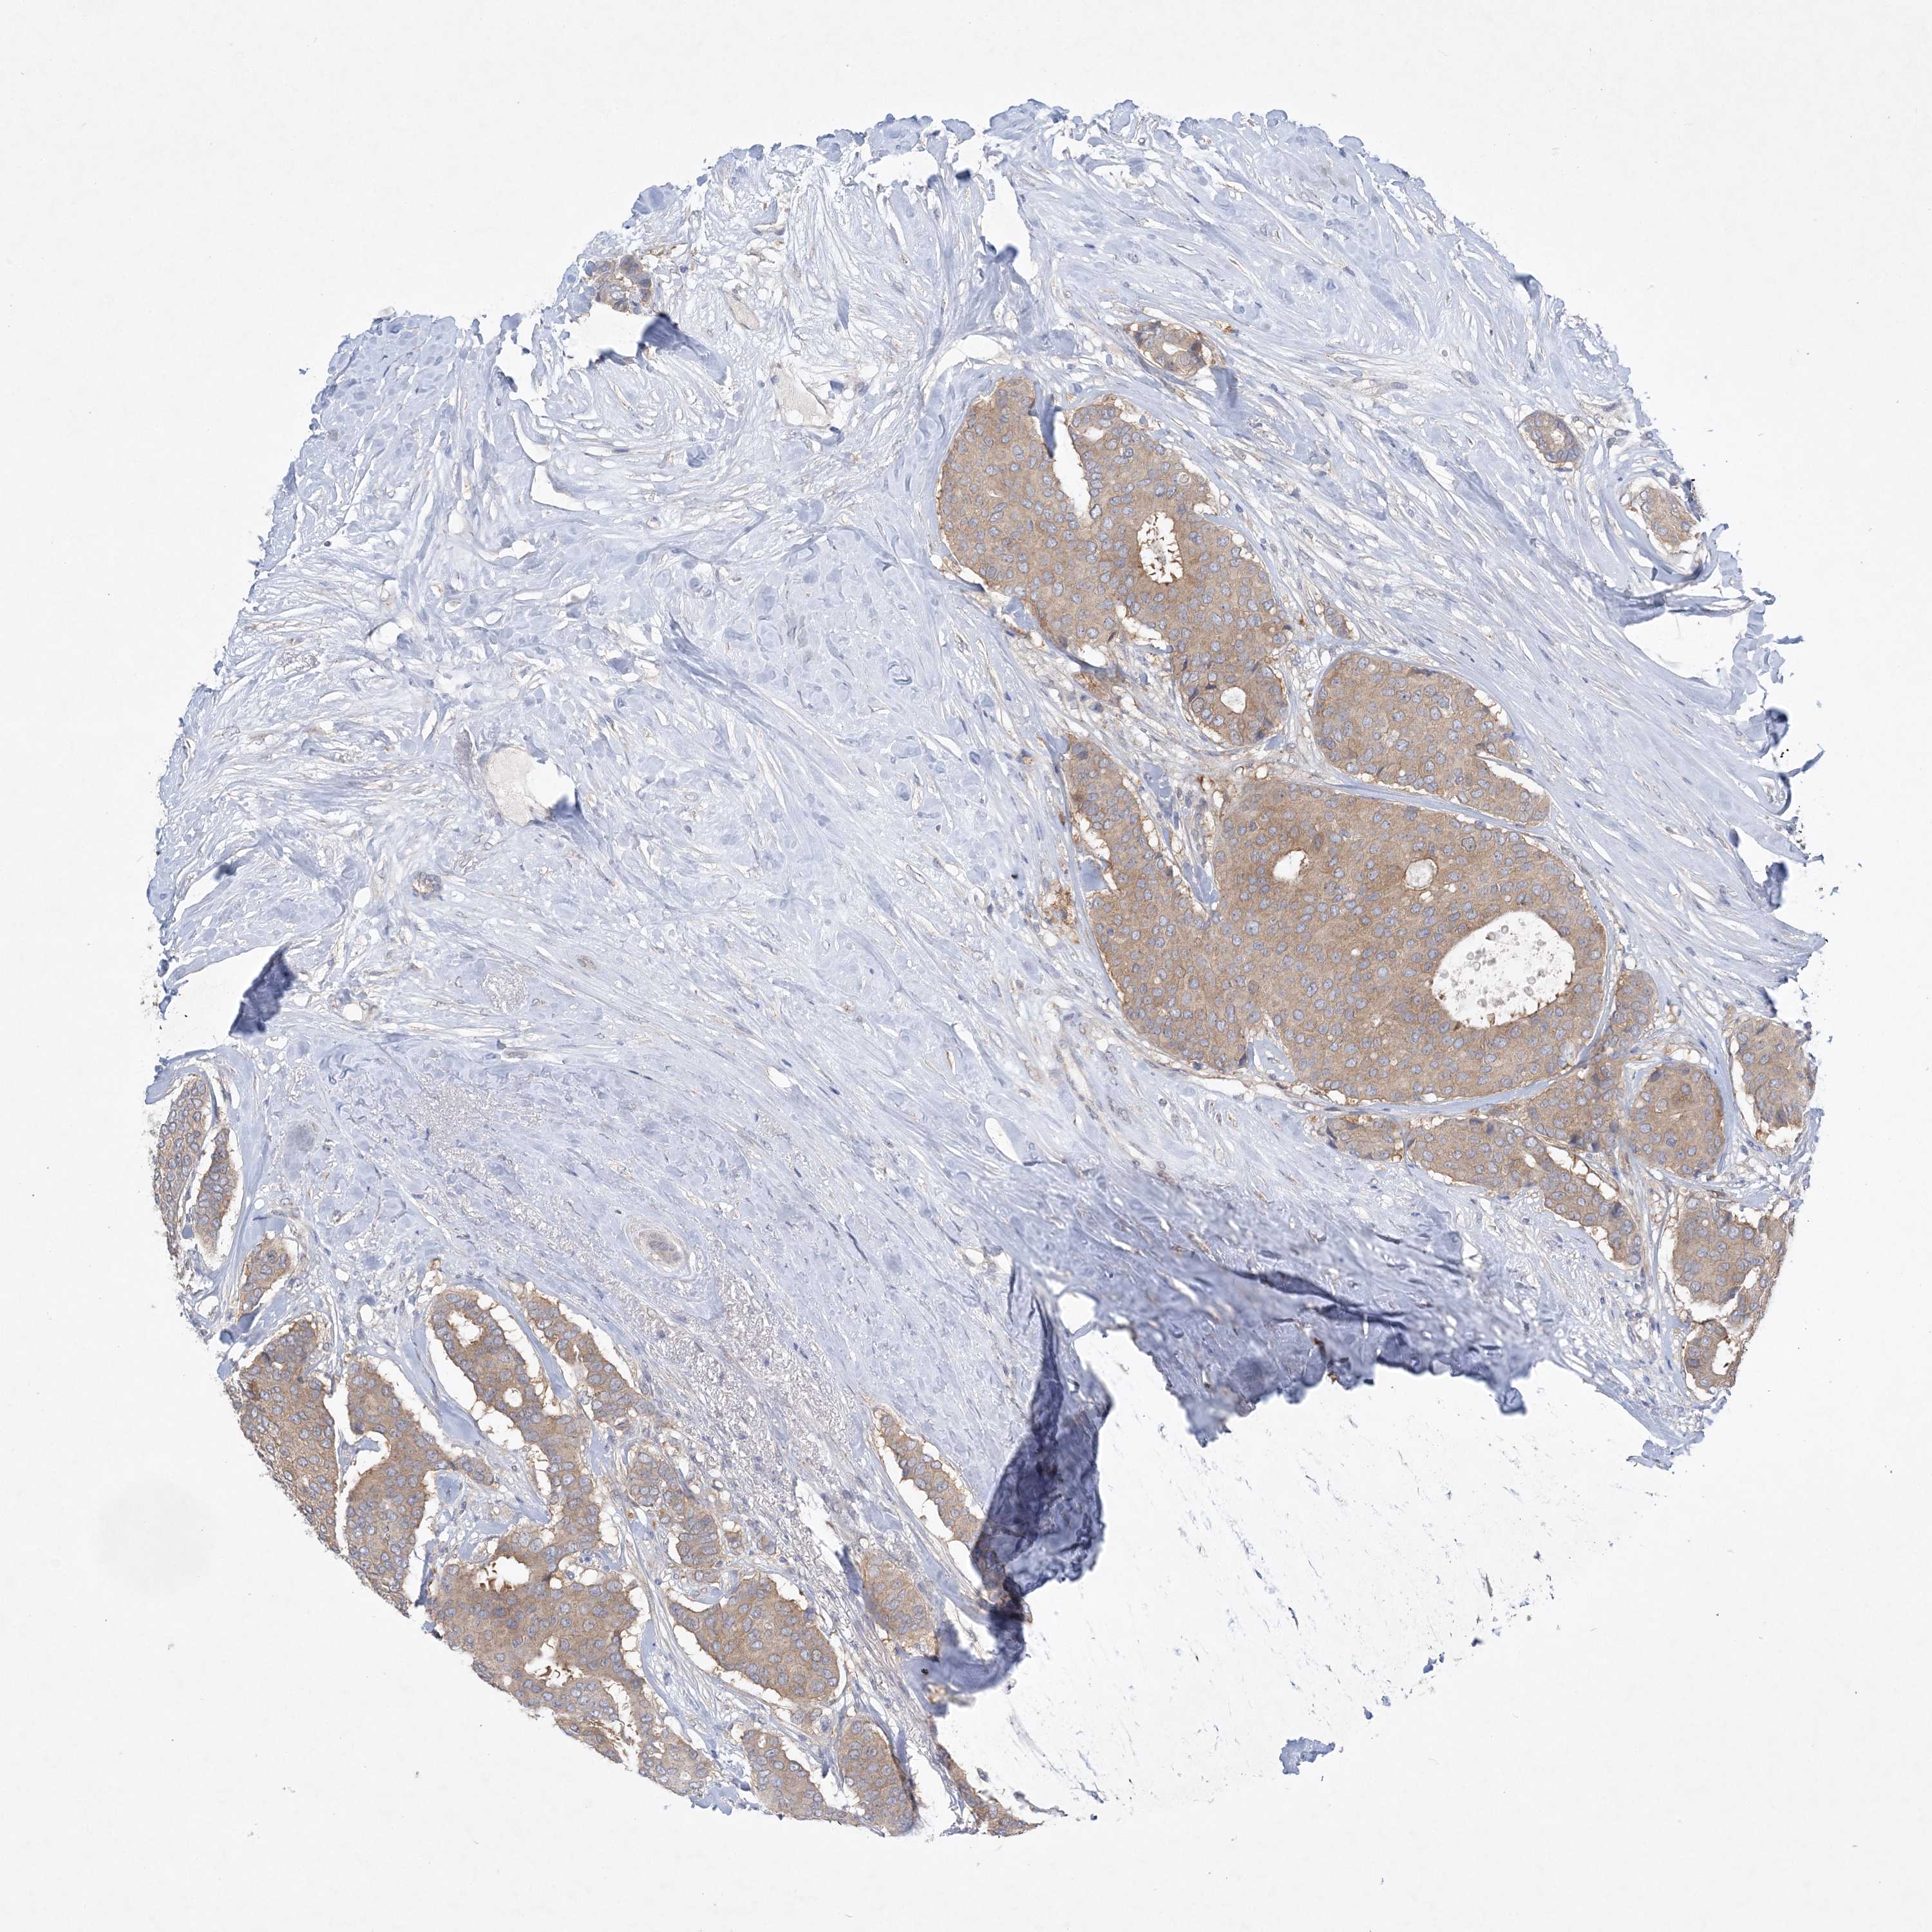

CANCER BREAST CANCER Show tissue menu

BRCA TCGA BRCA VALIDATION PROTEIN EXPRESSION

ANTIBODIES

AND

VALIDATION

Breast cancer

Human cancer